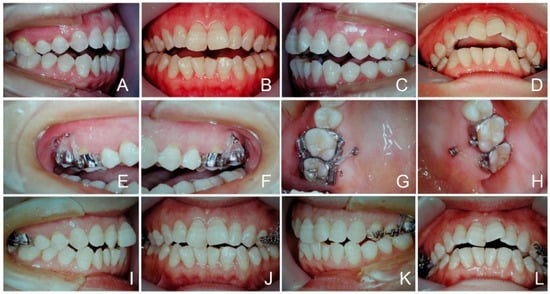

3.2. Case 4 (Total Intrusion, Figure 10 and Figure 11)